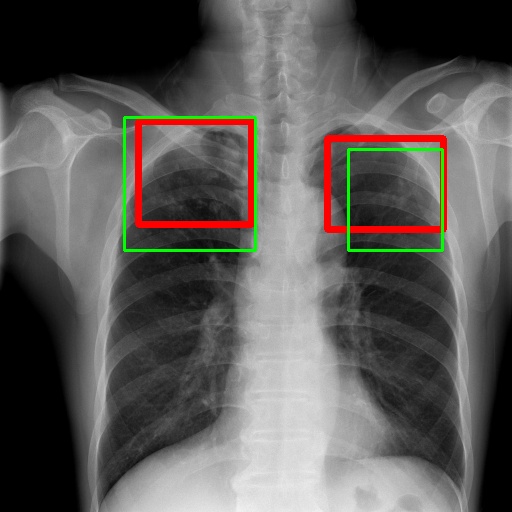

6.4 Visualization

To gain insights into the learning process of deep neural networks on CXR images, we visualize the feature map of SymFormer w/ RetinaNet at a scale of . To achieve this, we employ principal component analysis (PCA) to reduce the channels of the feature map to a single channel. The resulting single-channel map is then converted into a heat map for visualization purposes. The visualization of the learned features, along with the corresponding detection results, are presented in Fig. 6. Upon analysis, we observe that the visualization of healthy cases exhibits irregular feature patterns, indicating the absence of significant abnormalities. In contrast, the visualization of sick but non-TB cases displayed some discernible highlights, potentially representing the presence of lesions. For TB cases, the highlights in the visualization map align well with the annotated TB infection areas, thereby indicating the effectiveness of the proposed SymFormer in learning deep features for TB area detection. Furthermore, in Fig. 7, we offer qualitative comparisons between the proposed SymFormer and the baseline models for TB infection area detection. As evident, SymFormer consistently delivers superior qualitative detection results.